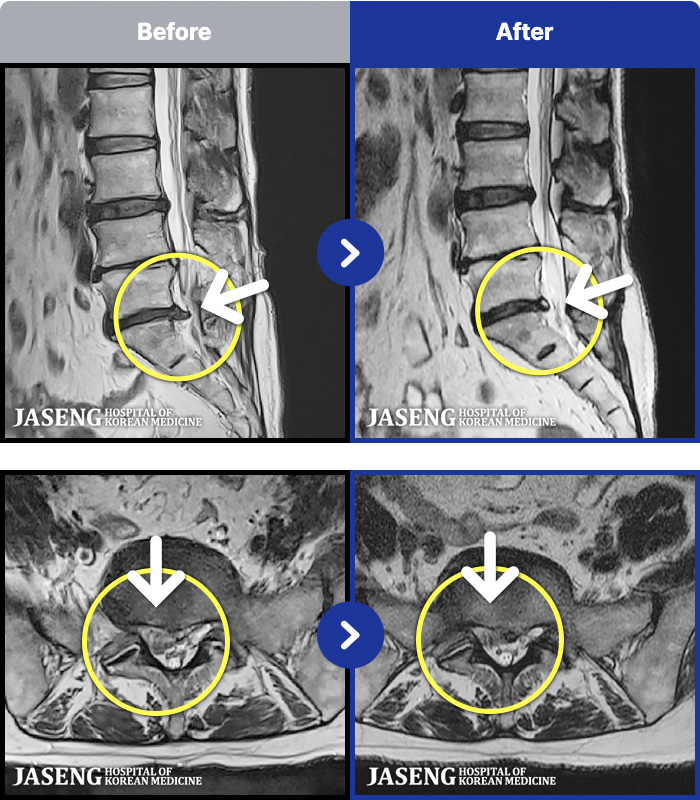

[ϻ] 24.07.25~25.08.01

ȯںп Ǹ ǿ ԿǾ, ο ġ ۿ Ƿ ġḦ Ͻñ ٶϴ.